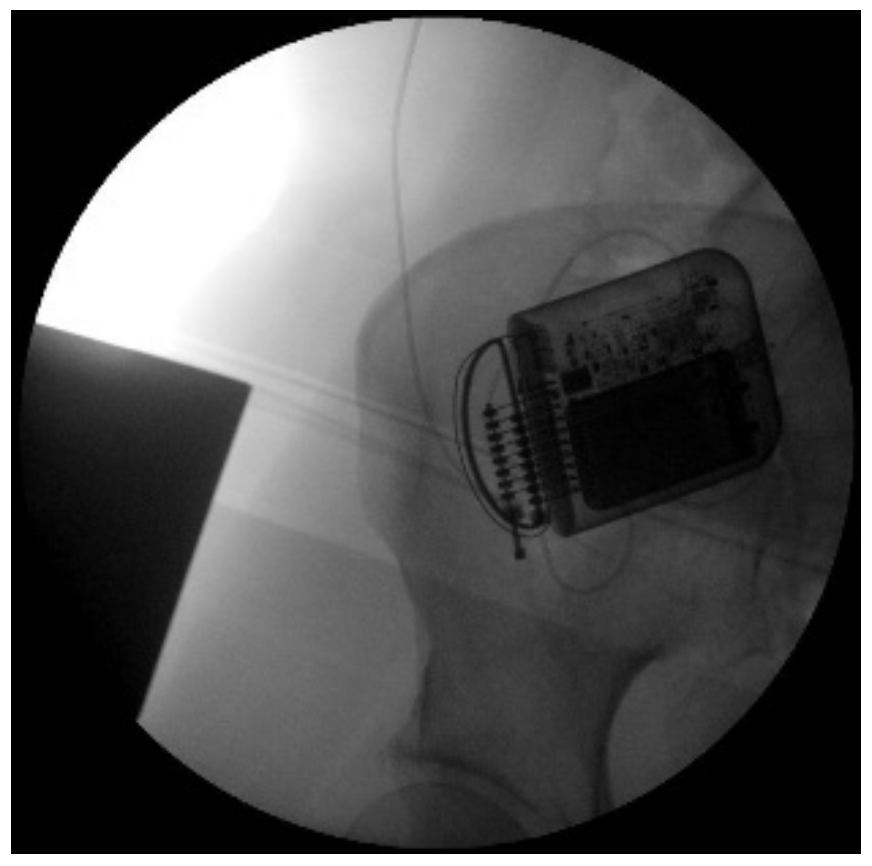

- -